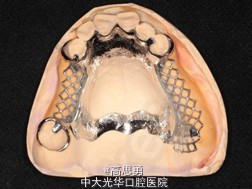

诊断: 1、牙列缺损(上颌肯氏II类I分类,下颌肯氏II类II分类) 2、#13慢性根尖周炎 3、#11、#12、#13、#21、#22、#23、#33、#42、#43、#44楔状缺损 4、慢性牙周炎 治疗计划 1、#13转牙体牙髓科做RCT 2、转牙体牙髓科对#11、#12、#13、#21、#22、#23、#33、#42、#43、#44楔状缺损 充填治疗 3、转牙周科进行牙周洁治 4、择期RPD修复 备选修复方案: 1、#13RCT后截冠后,上下颌覆盖义齿修复; 2、#13RCT后冠修复,上下颌可摘局部义齿修复; 3、#13RCT后树脂充填,上下颌可摘局部义齿修复; 4、#13拔除后,上下颌可摘局部义齿修复。 患者意愿:患者希望尽量保持#13的天然形态,要求费用尽量低,但能恢复正常咀嚼功能。 最终治疗方案:根据患者的年龄、身体状况、治疗周期、经济状况,患者最终选择方案5,即#13RCT后树脂充填,上颌结合卡环式可摘局部义齿修复;下颌可摘铸造支架式局部义齿修复。 治疗过程: 1、临床检查和#13树脂充填 对患者进行全面的口腔检查,用Z350树脂充填#13,调HE,抛光。 2、研究模型 调拌藻酸盐印模材料于2号成品托盘上取上下颌研究模,灌注石膏模型,研究分析、制定治疗计划,并制作个别托盘。 3、基牙预备 对#13近中、#23远中、#27近中、#34近中、#47近中常规制备支托凹,抛光。 4、工作模型 调拌藻酸盐印模材料于个别托盘上。做一定的边缘整塑,取上下颌研究模,灌注石膏模型。 5、试戴支架 检查支架的就位、固位可,无翘动,调HE,抛光,用蜡堤取颌位关系,上颌架,排牙,比色C4。 6、试排牙 检查义齿的就位、固位可,无翘动,观察人工牙的咬合状况,尖窝接触良好,正中颌位能重复,患者无诉不适,面容自然,外观满意。送加工厂充胶制作最终修复体。 7、试戴 检查义齿的就位、固位可,无翘动,咬合关系正确,利用咬合纸检查,上下颌尖窝接触均匀全面,抛光,患者表示满意,嘱注意事项,定期复诊。